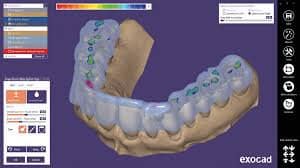

Diseño de férula para colocación de implantes de forma guiada en arco completo. Recomendada para casos de 4-8 implantes.